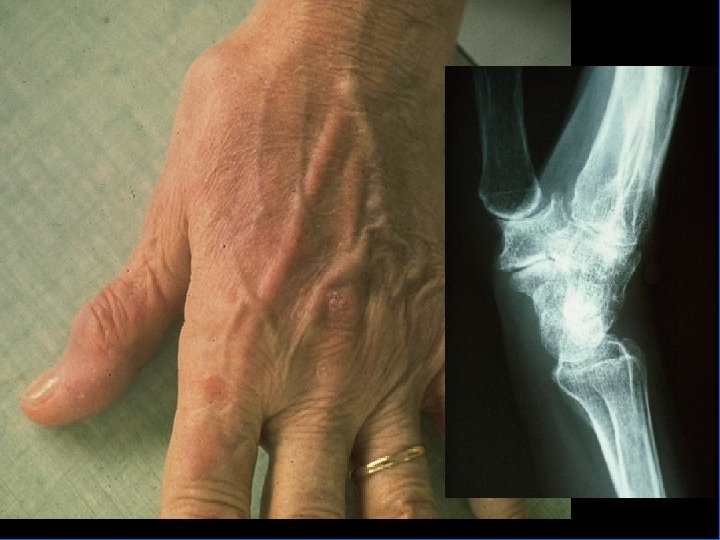

Quand faut-il évoquer le diagnostic ? • Développement à bas bruit de tuméfactions nodulaires parfois douloureuses : – des IPD entraînant des déformations importantes (en flessum ou latéralement) : les nodules d’Heberden. – des IPP : moins fréquente, caractérisée par les nodosités de Bouchard. – rhizarthrose : douleurs de la racine du pouce et la partie externe du poignet. Mobilisation de la trapézo-métacarpienne douloureuse et hypertrophiée, parfois le siège d’un petit épanchement

Comment faire le diagnostic ? • Le diagnostic est clinique : déformations typiques • Les radiographies : mains de face – pincement de l’interligne – une ostéophytose latérale en berge, très exubérante responsable des nodosités – géodes sous-chondrales